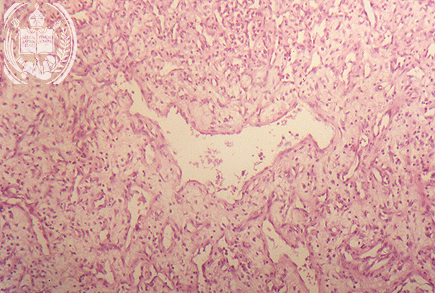

Abb. 52-B2: Angiomatoeses Fibrom

Der polypoese Tumor weist bei der histologischen Untersuchung ein lockeres Bindegewebe und zahllose kavernoese Blutgefaesse auf. HE-Faerbung.